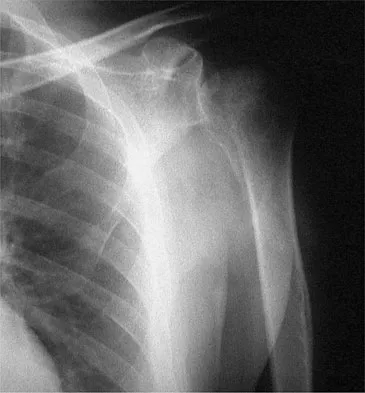

Question 18

A 25-year-old man injured his dominant shoulder after falling on his outstretched arm 4 months ago. Examination reveals that he cannot lift his arm above 90 degrees, and he has pronounced medial scapular winging. Management should consist of

Explanation